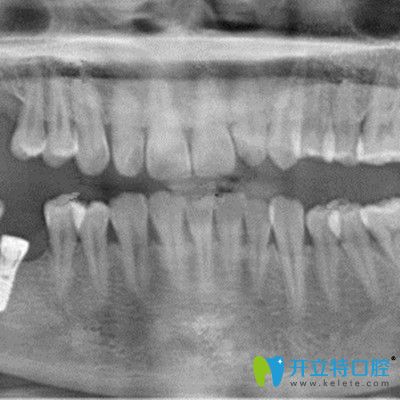

在吉林愛齒口腔做即刻種植牙拍片照片

再次到,譚醫(yī)生表示我的牙骨質(zhì)條件還是挺好的,當天就做了手術(shù),裝入了種植體,戴了臨時冠,整個手術(shù)過程大概持續(xù)了一個小時左右。因為做的是微創(chuàng)即可種植技術(shù),所以基本沒有痛感。